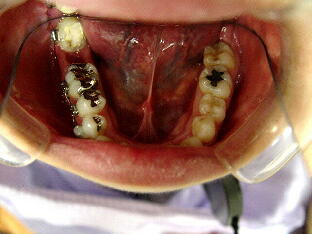

(2)初見では抜歯もしくは遠心根を抜去(ヘミセクション)を考慮しましたが、20代前半で

まだ若いため、約1年半をかけて根の治療を行いました。 ![]() ![]() ![]()

パノラマ画像:黒く写っている病巣が徐々に小さくなっていく様子が分かります。